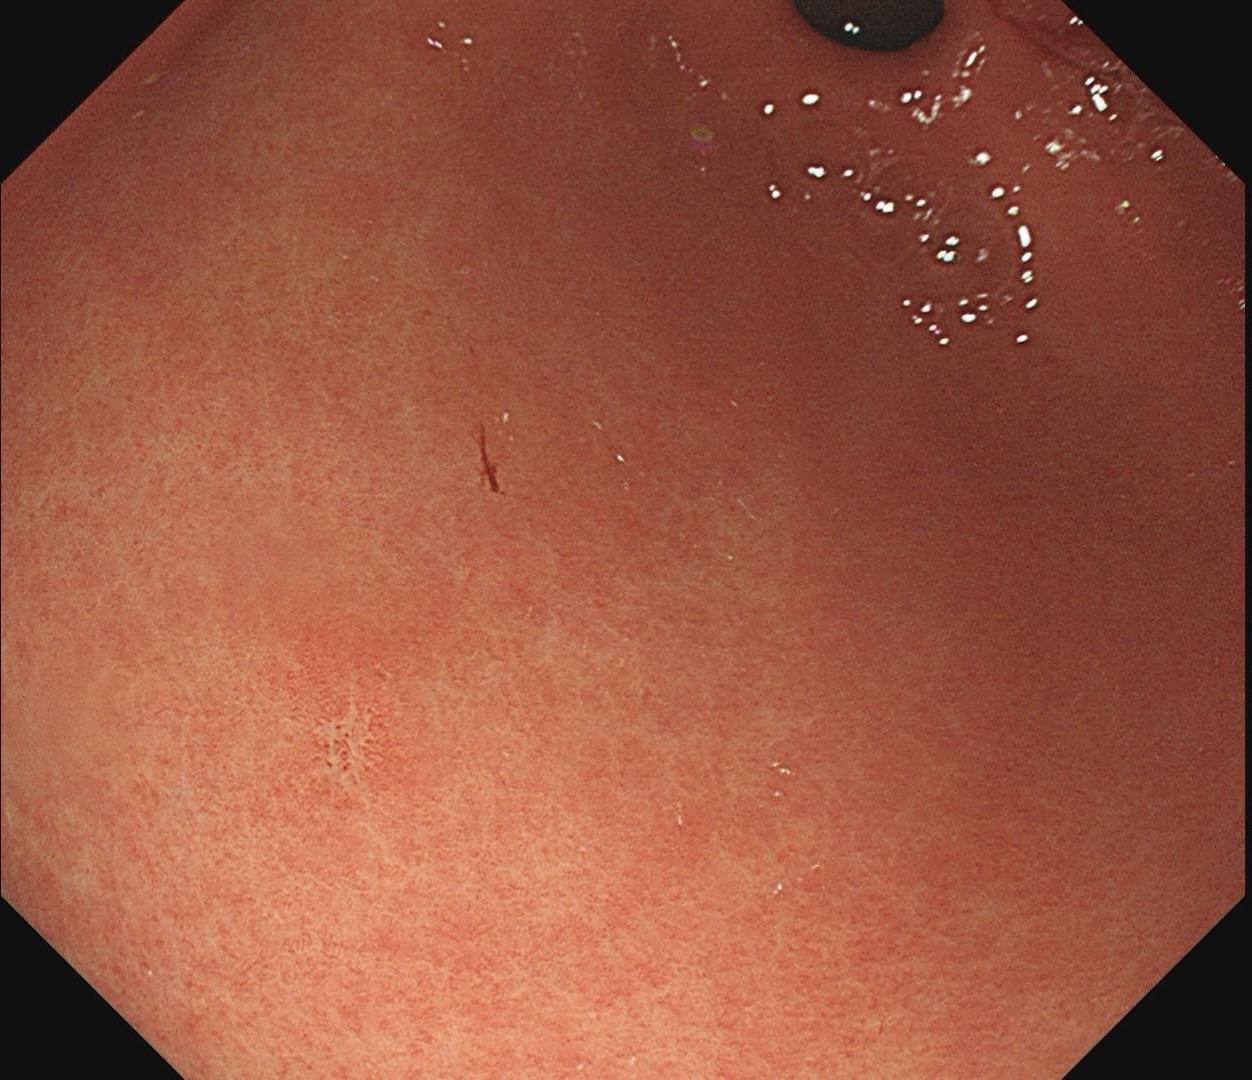

小小的糜烂一枚。这样的病灶,就算结果是阴性的,也很有意义~